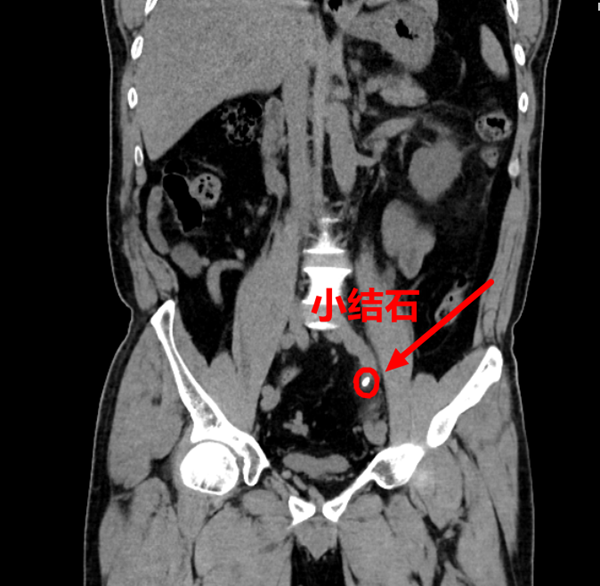

紧急检查结果印证了医生的担忧:CT提示韩先生左侧输尿管结石,且肾功能指标中,肌酐已飙升至336μmol/L(正常范围仅为57-97μmol/L),远超正常上限3倍之多,急性肾损伤已悄然发生。若不及时解除梗阻,毒素会在体内快速蓄积,不出多久就可能引发不可逆的肾衰竭,等待他的将是终身透析的痛苦。

手术室里,泌尿团队默契配合、争分夺秒,熟练开展急诊输尿管镜下钬激光碎石取石术。纤细的输尿管镜精准抵达结石梗阻部位,结石约6毫米,钬激光精准发力,将堵塞尿路的结石击碎取出,随后顺利置入支架管,确保尿液能够通畅引流。整个手术仅用了10多分钟,当尿液顺利流出的那一刻,所有人都松了一口气,这根单侧“生命尿道”,终于被成功开通,当天共引流出尿液1900ml。